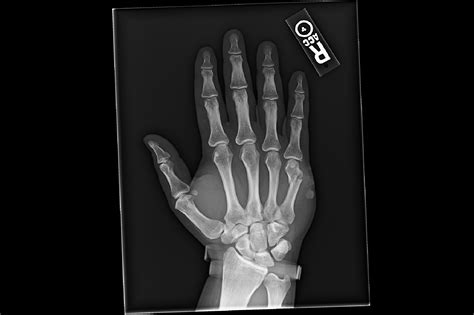

A broken hand, often diagnosed through an X-ray, involves a fracture in one or more of the bones in the hand. The hand is composed of 27 bones, including the metacarpals, phalanges, and carpals. Each of these bones can be susceptible to fractures, which can range from minor cracks to severe breaks.

• X-rays: X-rays are the primary imaging tool used to confirm the presence and type of fracture. They provide detailed images of the bones and can help determine the severity of the injury.

Metacarpal Fractures Fractures in the metacarpal bones, which connect the fingers to the wrist. Punching a hard surface, falls, or direct blows.